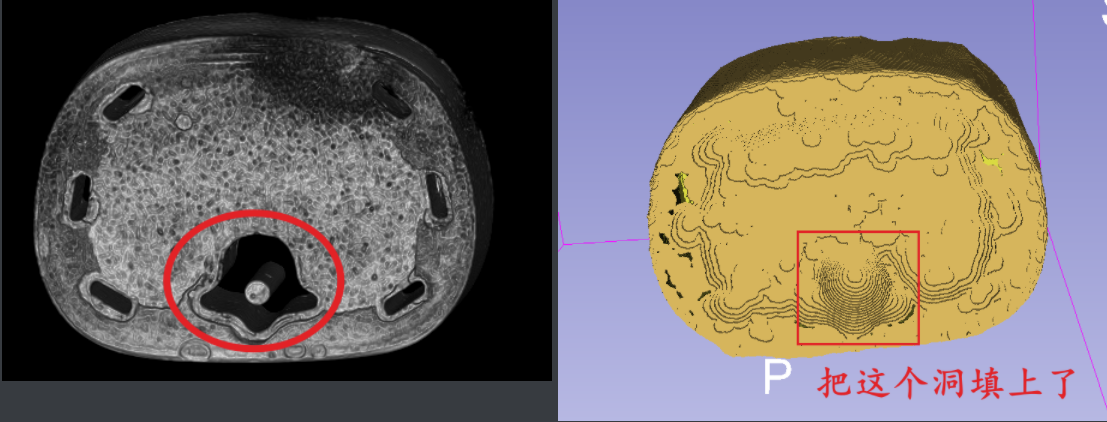

根据水密性可以填充“孔洞”,如下图所示:

上图中3d建模后红色框原本是空的,不满足水密性,检测出来之后填充就会一定程度上填充这个洞。这才是水密性的用途。